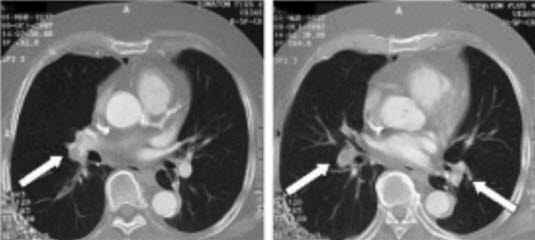

Lungeemboli - spiral CT

Spiral CT: Pilene viser okkluderende trombe i underlappsarteriene begge sider